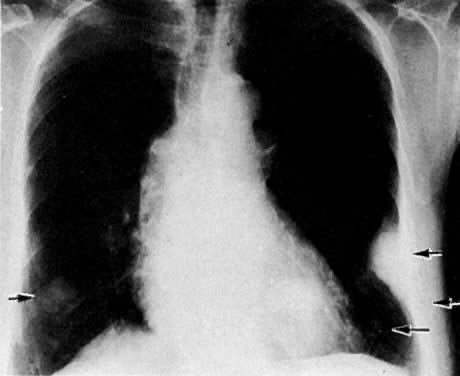

Multiple metastatic nodules in a patient with uterine leiomyosarcoma. Note pleural effusion in the left costophrenic angle.

Endometrial carcinoma metastatic to both lower lung fields (lower left and lower right arrow). There is also destruction of the eighth rib (middle arrow) and an extrapleural lesion (upper arrow) on the left.

Posteroanterior chest film in a patient with metastatic cervical carcinoma shows multiple cavitating metastatic lung lesions.